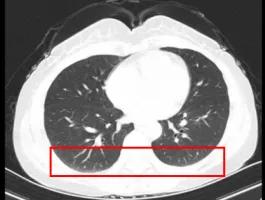

根据患者临床症状(手指雷诺现象、手指肿胀及皮肤增厚)(如图1-1)、胸部CT发现早期轻度肺纤维化(如图1-2)、SSc特异性抗体(抗着丝点抗体强阳性)(如图1-3)等情况,考虑可以明确诊断为“系统性硬化症”。